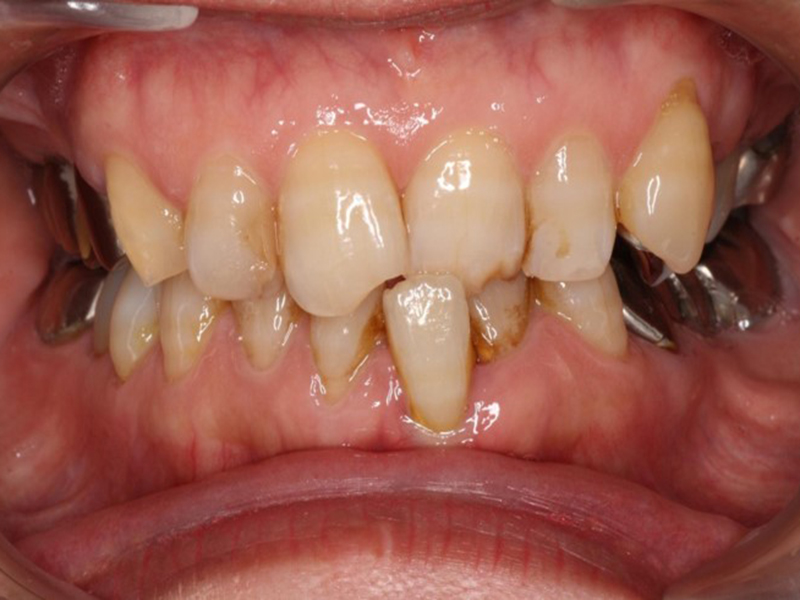

before

経過

after